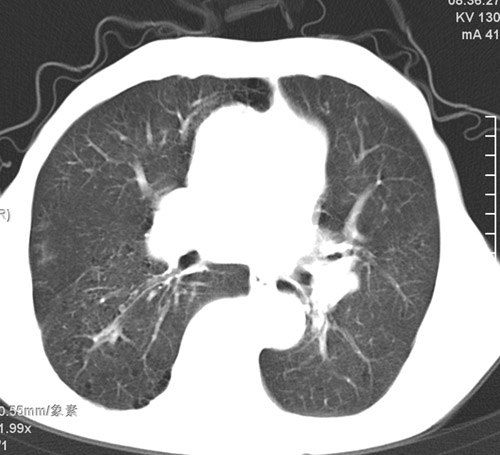

标题: CT17529:男 76 胸背部不适半月 胸透支气管炎 行CT检查 [打印本页]

标题: CT17529:男 76 胸背部不适半月 胸透支气管炎 行CT检查

意见 老年肺 少许炎症 肺大泡 右肺门略大 但支气管通畅  请各位高手指教如何下意见

间质纤维化伴少许炎症!另:肺大泡形成!

支持楼主意见,右肺门略大,可能为肺动脉增粗.

慢支肺气肿,肺动脉高压.